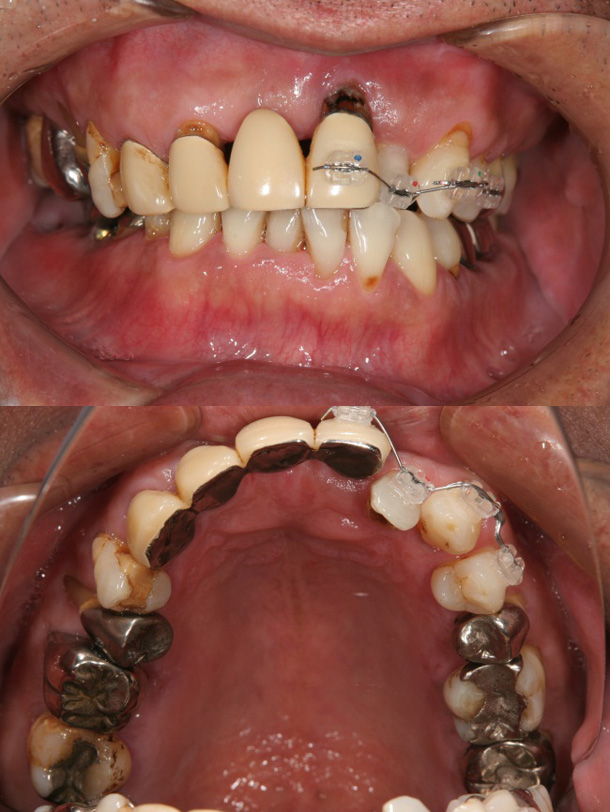

症例6:叢生による矯正治療後、上顎前歯・臼歯部をオールセラミッククラウンにて審美修復した症例

主訴:右下の冠がはずれた、前歯で咬めない

年齢:43歳

診断:上顎前歯酸蝕症による舌側エナメル質欠損、上下顎叢生、臼歯部反対咬合

装置:上下顎ブラケット装置

治療期間:2年1ヶ月(矯正治療)(来院回数24回)

抜歯:右下顎大臼歯の2本(むし歯によ)保存不可のため→インプラント治療を実施)

費用:750,000円+税

矯正前

矯正後

オールセラミックSET後